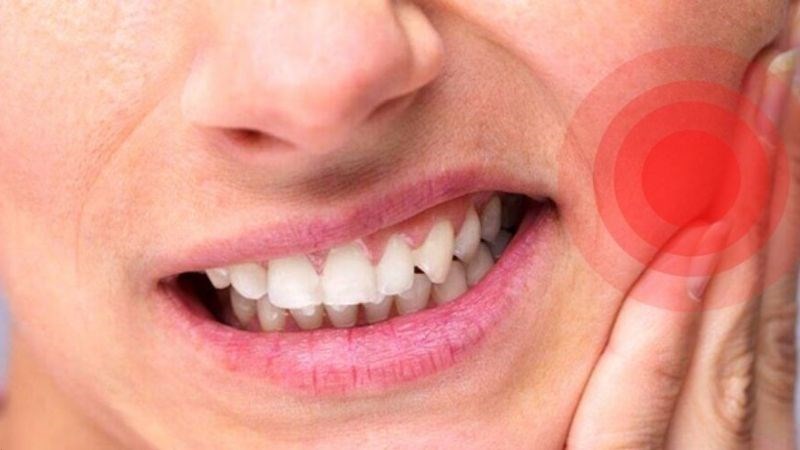

Sốt

Việc bị sốt sau nhổ răng là khá phổ biến. Tuy nhiên, hãy đảm bảo rằng nhiệt độ cơ thể của bạn không được vượt quá 38 độ C.

Nếu sốt đi kèm một số dấu hiệu khác như đau, khó nuốt hoặc khó thở, chảy máu liên tục không ngừng, sưng ngày càng nặng thêm,… là biểu hiện của nhiễm trùng. Khi đó, bạn cần liên hệ với nha sĩ để được hỗ trợ kịp thời.

Việc bị sốt sau nhổ răng là khá phổ biến